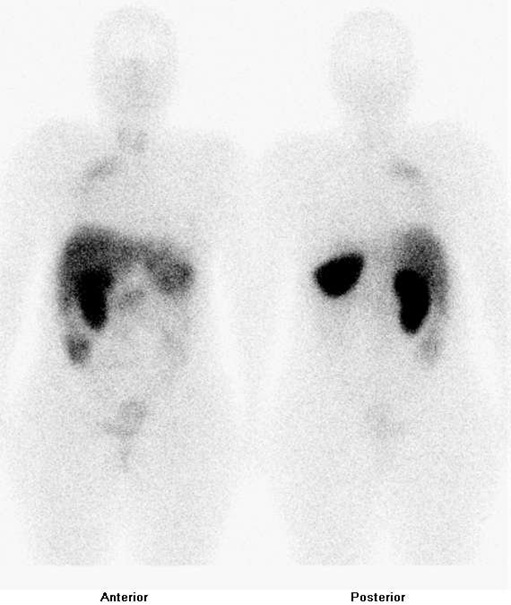

Po příslušné přípravě jsme provedli planární celotělovou scintigrafii a tomografickou scintigrafii hrudníku a horní části břicha za 4 hod.

(obr. 1, 2), dále celotělovou scintigrafii (obr. 3) a tomografickou scintigrafii hrudníku a horní části břicha

(obr. 4) za 24 hod. po i.v. podání 150 MBq analogu somatostatinu značeného

111In (přípravek OctreoScan firmy Mallinckrodt Medical) na dvouhlavé tomografické kameře Symbia T2 firmy Siemens (bohužel pro poruchu CT nebylo možno provést CT vyšetření s fúzí SPECT/CT). Je patrná fyziologická depozice radioaktivity ve slezině, pravé ledvině, močovém měchýři, střevech a difuzně v játrech a patolog. ložisko zvýšené depozice radiofarmaka v horní části pravé plíce.

/Obr.č.1: Celotělová scintigrafie v přední a zadní projekci 4 hod. po aplikaci OctreoScanu /

/Obr.č.3: Celotělová scintigrafie v přední a zadní projekci 24 hod. po aplikaci OctreoScanu /